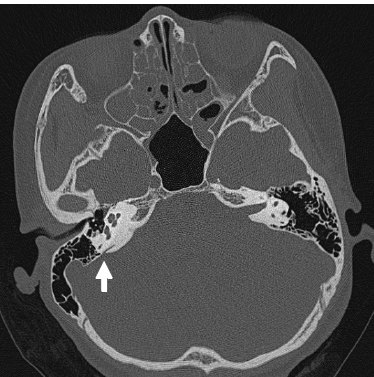

大前庭导水管综合征的ct影像学诊断

大前庭导水管综合征的ct影像学诊断 - 好大夫在线